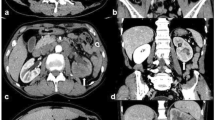

The results of qualitative data are shown in Table 1; Figs. 1, 2, 3 and 4. RO and ccRCC had significant differences in enhancement inversion and persistent low sign (p < 0.05). RO and non-ccRCC revealed significant differences in the typical stellate pattern, enhancement inversion and calcification(PTP) (p < 0.05). The remaining parameters between RO and RCC overlapped significantly.

Schematic diagram of the qualitative features. a 66-year-old male with RO. The CHA of tumor shows as a typical stellate pattern (arrow). b A 59-year-old female with RO. Calcification within CHA is observed(arrow). c A 62-year-old female with ccRCC. Calcification within PTP is observed(arrow). d A 55-year-old female with ccRCC. Pseudocapsule sign is discovered at the edge of tumor (arrow). CHA Central hypodense area, ccRCC Clear cell renal cell carcinoma, LSR Long-to-short-axis ratio, PTP Peripheral tumor parenchyma, RO Renal oncocytoma